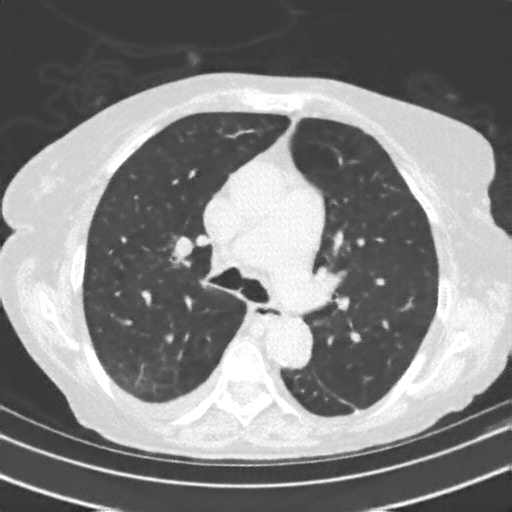

Generated VENOUS CT scan (A→B translation)

Full window (WL 1023.5, WW 4095 β†’ Low βˆ’1024, High +3071)

Lung window (WL -600, WW 1500 β†’ Low βˆ’1350, High +150)